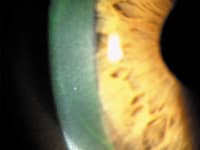

| Figure 2. VLK resolution and small intracorneal hemorrhage. | |

Case 1, Visit 2 Our patient cancelled her first appointment and returned two weeks later, reporting less redness and no irritation OS. The large corneal infiltrate showed significant improvement, was mildly elevated, had trace staining and was vascularized throughout. We noted a small intracorneal hemorrhage at this visit (Figure 2). We instructed the patient to continue the ocular lubricant and to discontinue the steroid. We advised her to return in one week for a comprehensive examination and contact lens fitting.

We also billed external ocular photography, 92285 to show resolution of the VLK and to document the intracorneal hemorrhage.